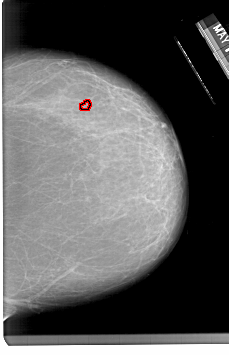

A_1333_1.RIGHT_MLO

RIGHT_MLO LINES 6451 PIXELS_PER_LINE 4306 BITS_PER_PIXEL 12 RESOLUTION 43.5 OVERLAY

FILE: A_1333_1.RIGHT_MLO.OVERLAY

TOTAL_ABNORMALITIES 1

ABNORMALITY 1

LESION_TYPE CALCIFICATION TYPE PLEOMORPHIC DISTRIBUTION CLUSTERED

ASSESSMENT 4

SUBTLETY 2

PATHOLOGY BENIGN

TOTAL_OUTLINES 1

BOUNDARY